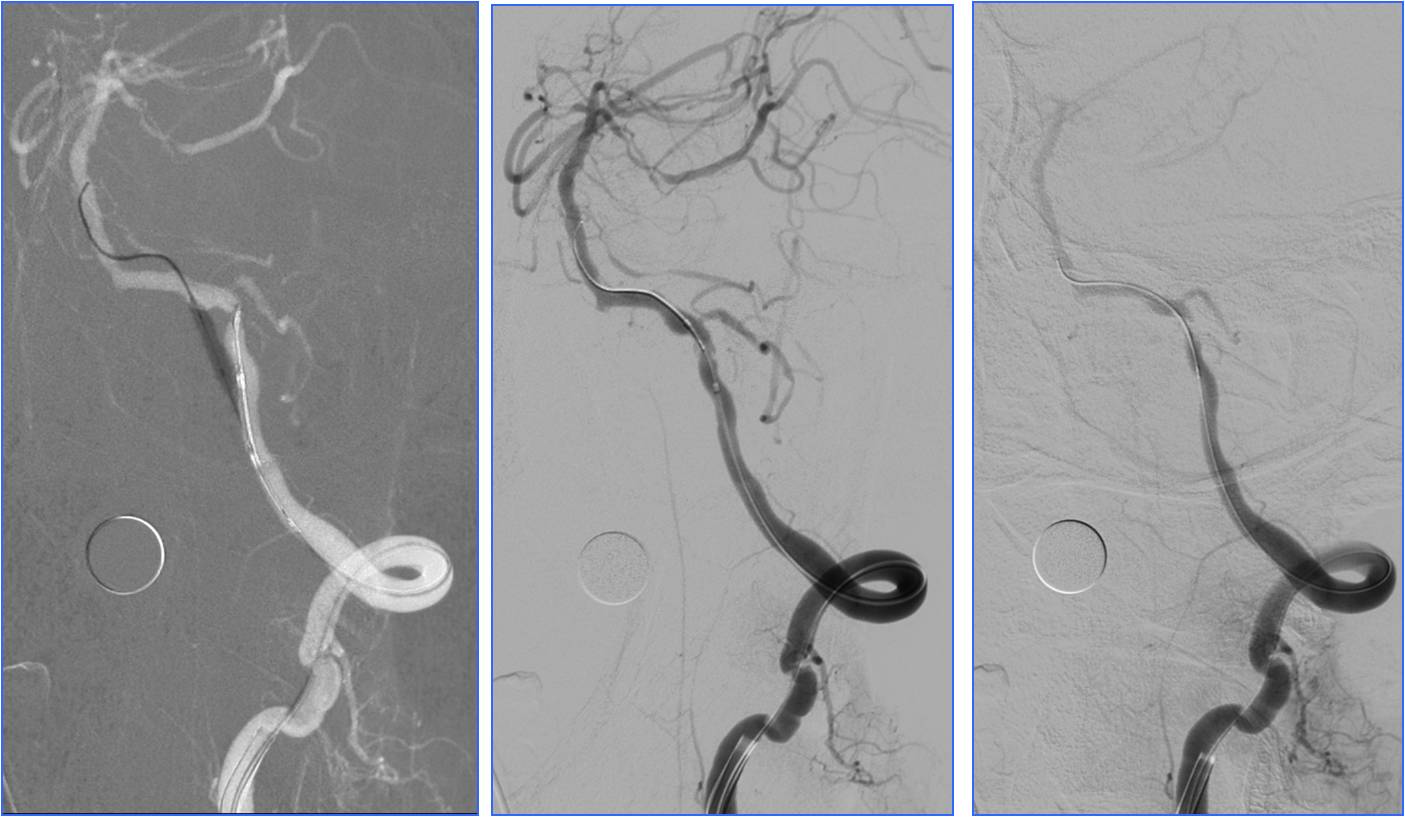

Case6 术后呼吸功能衰竭

》54岁,男,既往脑梗死、高血压病、糖尿病

》因头晕伴呕吐2天,9:50到达急诊

》10:08完成头CT检查

》15:30突发心跳骤停,行心肺复苏、气管插管

》NIHSS 30分

》15:55头MRA检查

》17:00行股动脉穿刺

》18:50结束手术

》术后24h NIHSS 10分

▼左椎动脉颅内段闭塞,脊髓前动脉代偿

▼右椎动脉颅外段闭塞

▼取栓后左椎动脉V4段残留狭窄

▼球囊成形,狭窄改善,不能维持

▼Wingspan支架置入

》11.30 13:00拔气管插管后不能呼吸,呼吸动度差,面部青紫,重新插管,spO2最低20%,意识不清,2小时后恢复。

》12.3 10:00再次拔管后仍不能呼吸,插管

》12.3 16:00行经皮气管切开。

》12.5 转普通病房后因血压高应用硝普钠后血压降至50mmHg,呼吸困难,青紫,昏迷,应用呼吸机后意识恢复。

》12.14自动出院,12.15死亡